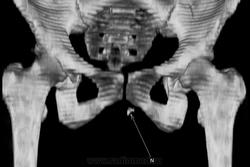

Инородное тело. Хирургическая игла.

Хирургическая игла, которую оставили гинекологи.

Да, гинекологи сами почуяли неладное и отправили пациентку на исследование. Операция была по поводу кисты левой бартолиневой железы. Со слов пациентки, ей до этого делали УЗИ, но ничего не обнаружили. Расположена она в толще большой половой губы, в преддверии влагалища.